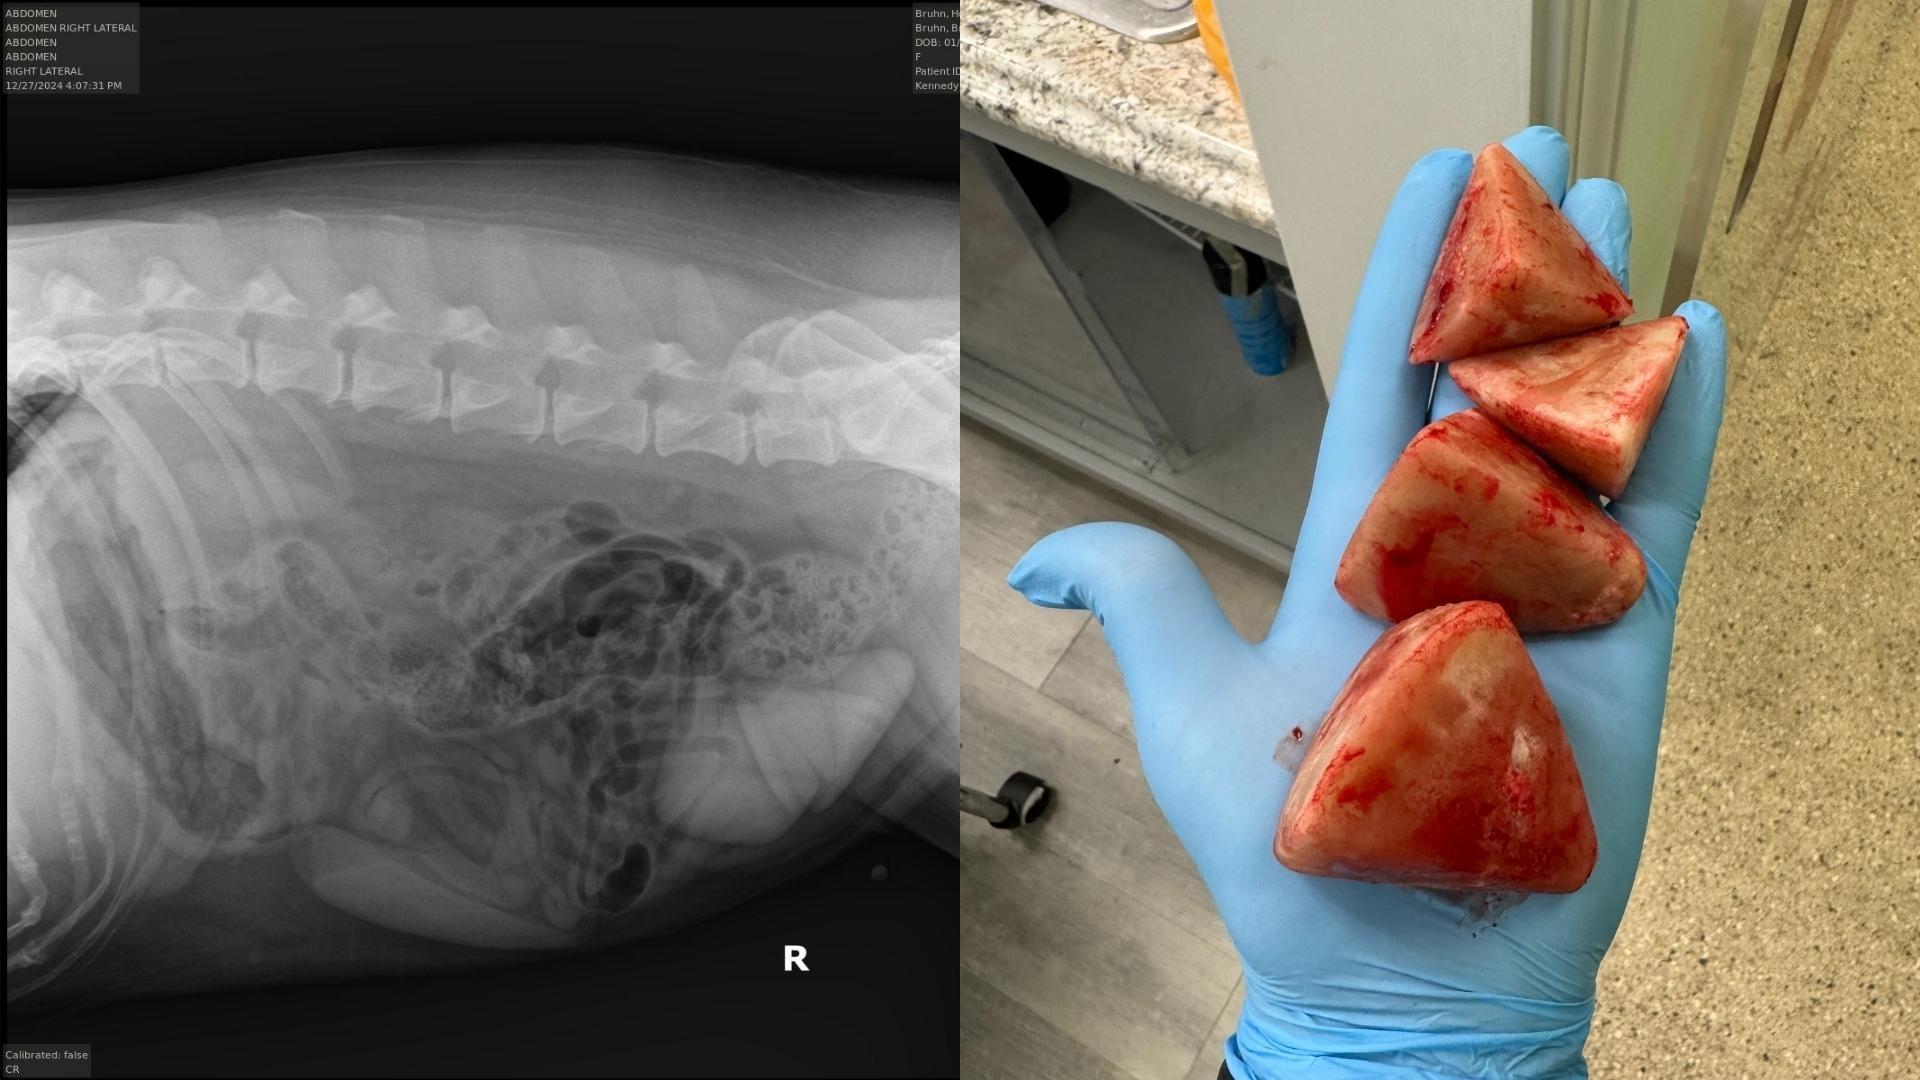

Foreign Body Removal

Clears blockages from the gastrointestinal tract (yes, even swallowed toys or binkies!).

Lunchbox, the dog pictured here, at 14 binkies!